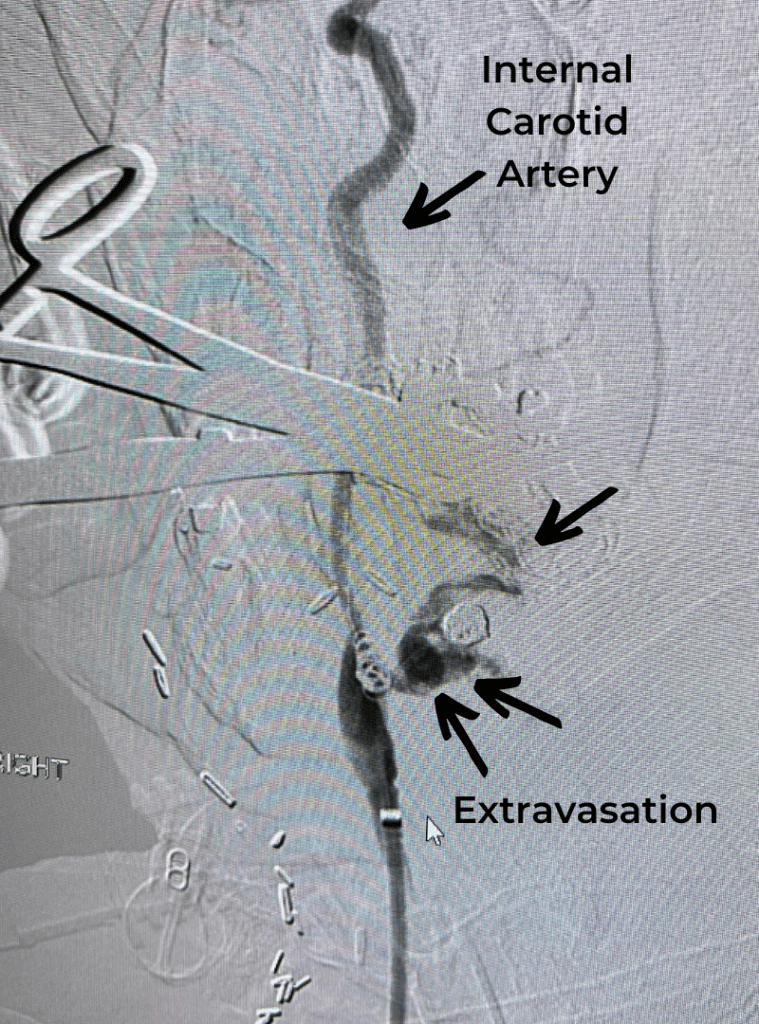

Endovascular:

CME:

Symptomatic Near-Occlusion of the Carotid Artery

Author: Jonathan L. Brisman M.D., F.A.C.S., Read More!